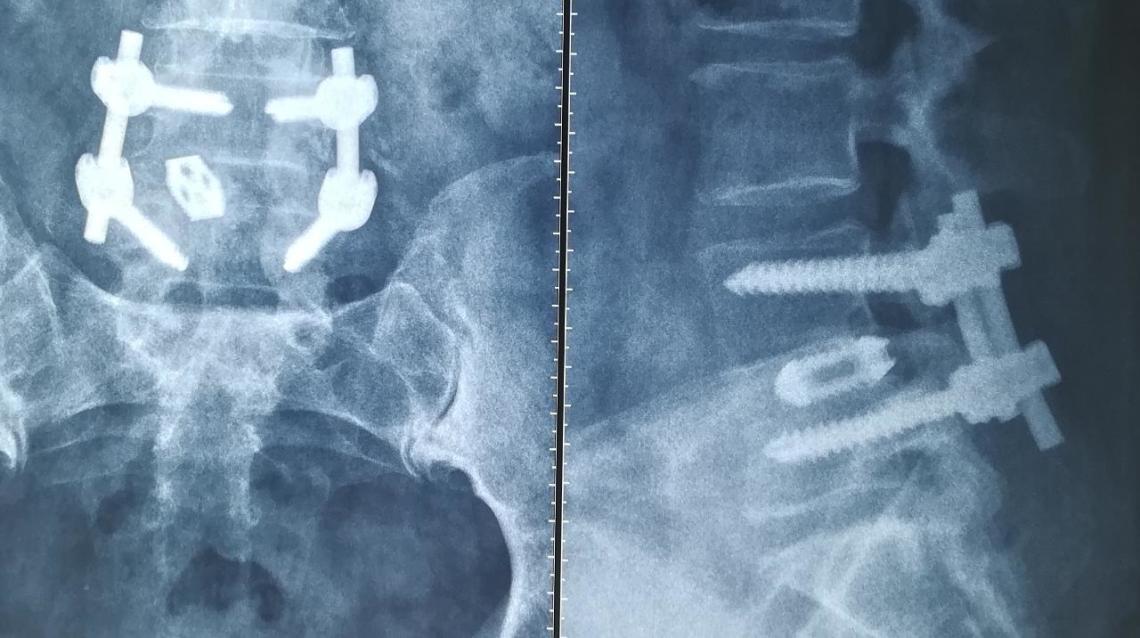

Explore spinal indentation, its causes, symptoms, and how imaging findings can impact clinical outcomes Since thecal sac houses spinal cord and cauda equina, it cushions them against damage from other spinal structures What is Thecal Sac Indentation? The thecal sac is a protective membrane that encloses the spinal cord and cerebrospinal fluid

Thecal Sac Mri. The condition may also be noted as a bulging disc encroaching on the thecal sac or a herniated disc indenting the thecal sac "Cloverleaf" or "trefoil" shape of the spinal canal for indentation of posterolateral thecal sac and severe central canal stenosis